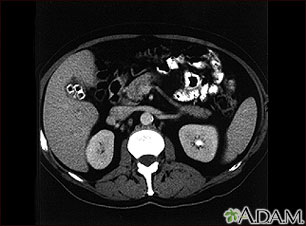

Tests used to detect gallstones or gallbladder inflammation include:

- Ultrasound, abdomen

- CT scan, abdomen